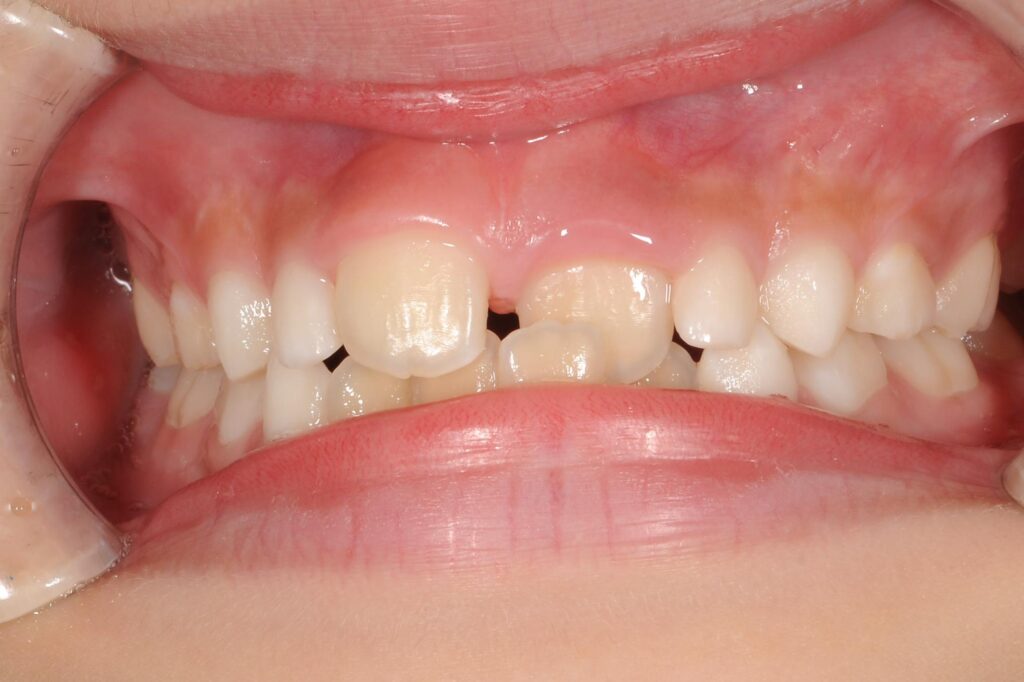

まずは術前の状態です。

【矯正前の状態】

問題点は、写真向かって右の前歯が下の歯に噛みこんでしまっています。

この状態を放置すると、上の歯の骨の成長を阻害し、大人になった時にそこだけへこんでしまいます。

早急にこの状態を解除する必要があり、治療開始することになりました。